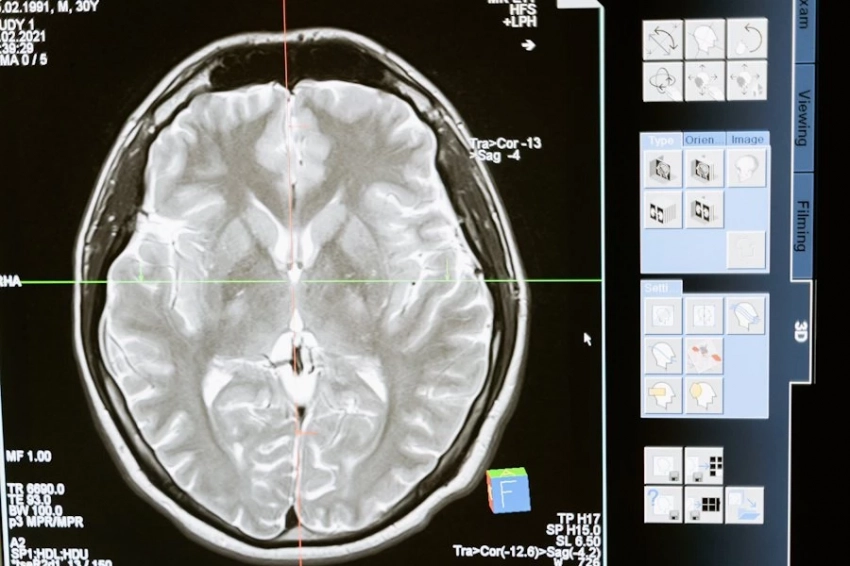

Группа японских исследователей проанализировала данные более 8700 человек в возрасте старше 65 лет. Участники исследования прошли МРТ-обследование головного мозга, которое позволило оценить общий объем мозга и состояние пяти его различных областей. Параллельно собиралась информация о количестве потребляемого зеленого чая и кофе.